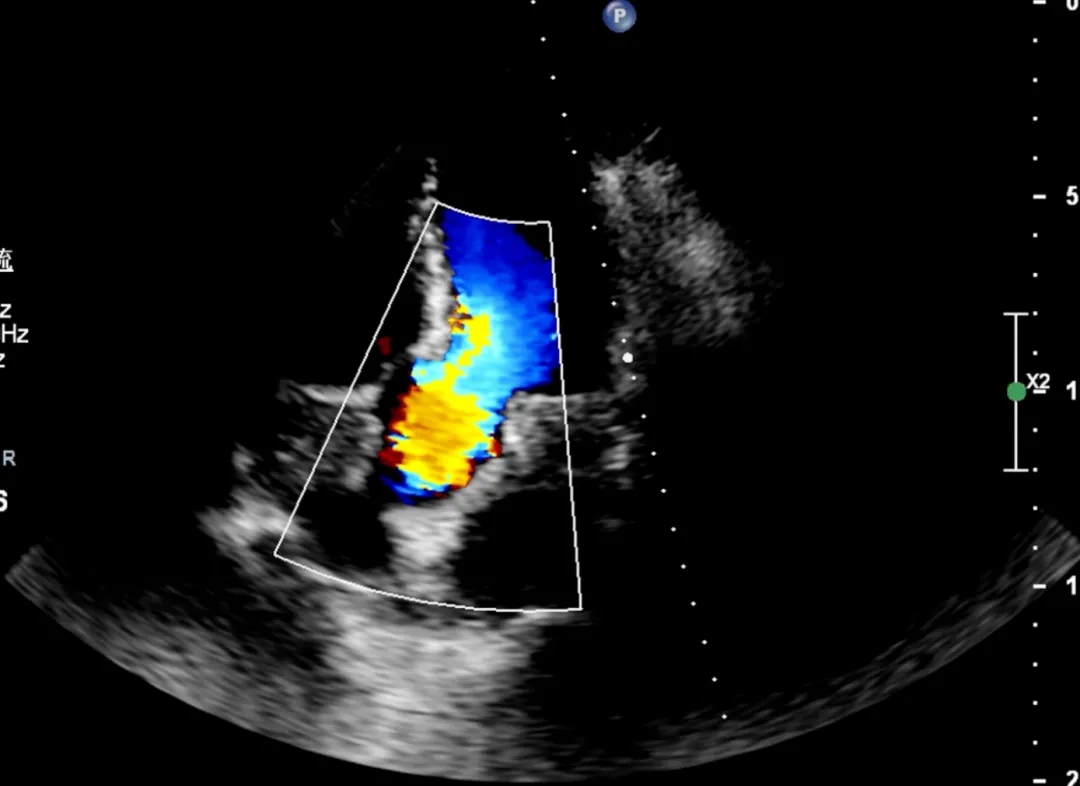

2025-5经食道超声心动图检查:

各角度探查左心耳内未见血栓回声。房间隔中段回声纤细,向右房侧膨凸,大小约26x12mm。

第二房间隔呈“搭错样”改变,通道宽约2.8mm,长约12mm。

CDFI:示房水平见左向右分流信号。室间隔连续完整。未见心包积液,无血栓及赘生物。余结构请参阅经胸超声心动图。

超声提示:

房间隔膨出瘤形成

卵圆孔未闭

房水平左向右分流

左心耳内未见血栓回声

2025-5超声右心声学造影检查:发泡实验阳性-心房水平可见右向左分流